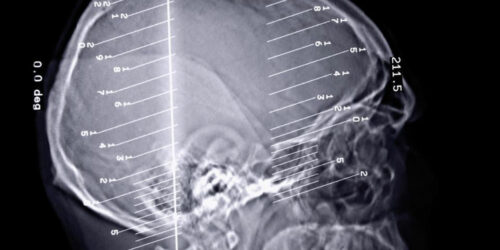

An overview of the types of epilepsy seizures

The human body can perform all its functions seamlessly when every organ of the body works in unison to perform the task. A slight change in the functions of the organ can disrupt the entire functioning of the body. Epilepsy seizures are a kind of disorder that occurs when we there is a problem in our brain’s electrical system.